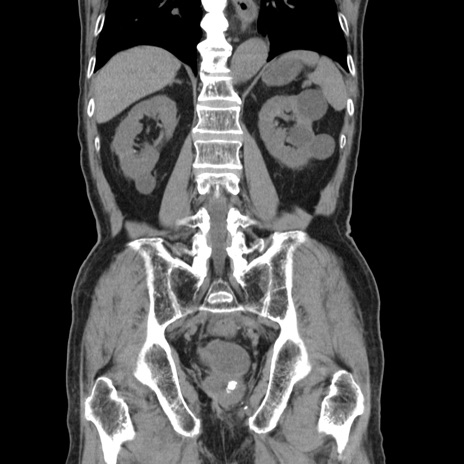

横断像